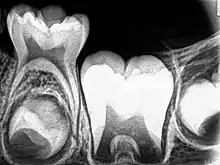

_showing_Deciduous(Milky_or_Primary)_Tooth_75_and_developing_crown_of_Permanent_or_Secondary_Teeth_35%252C_36_and_37.jpg.webp)